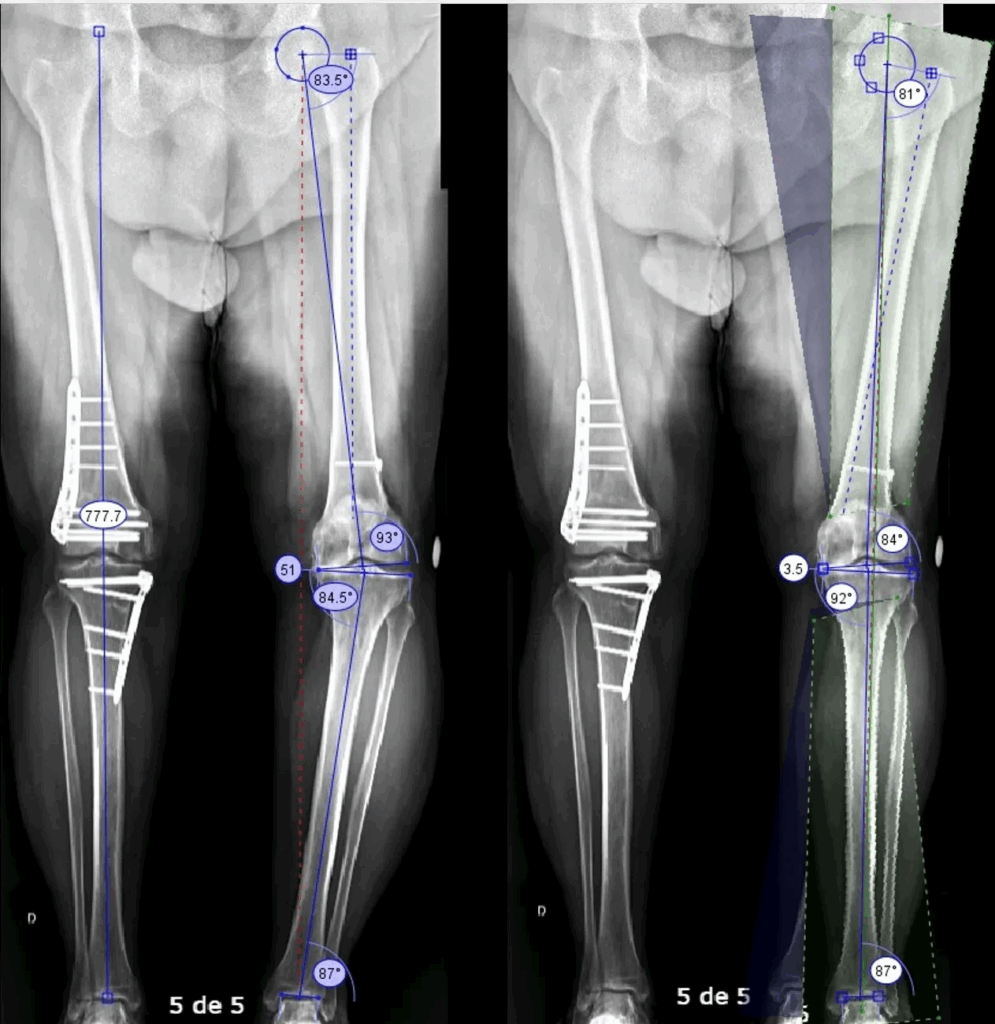

- Osteotomia: corrige o alinhamento do joelho, redistribuindo o peso. É como alinhar um carro para evitar desgaste irregular do pneu.